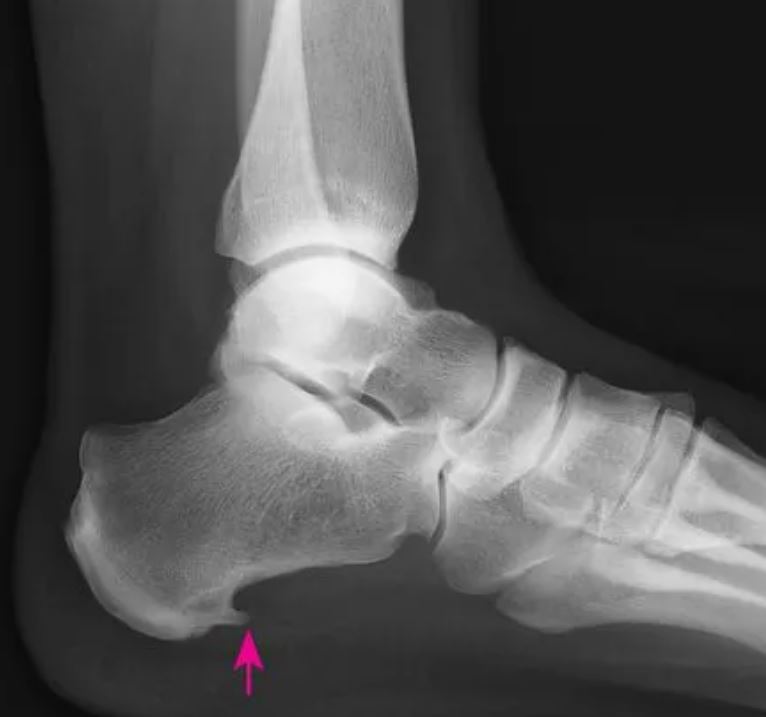

1.X线检查:多无阳性所见,部分患者可见跟骨结节跖侧有骨刺。